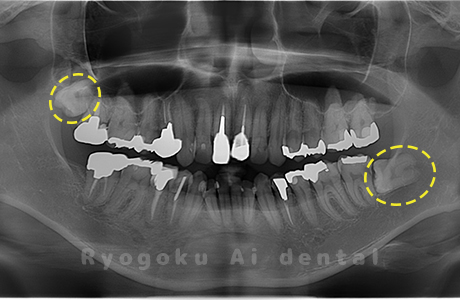

-

- 原因

- 下顎左右の埋伏の親知らず

- 治療内容

- インプラント治療は他院でおこなっており、当院で下顎左右の埋伏の親知らずを抜歯したケースです。

<リスク・副作用>

手術後は痛み、腫れ、痺れなどの副作用が生じる場合があります。